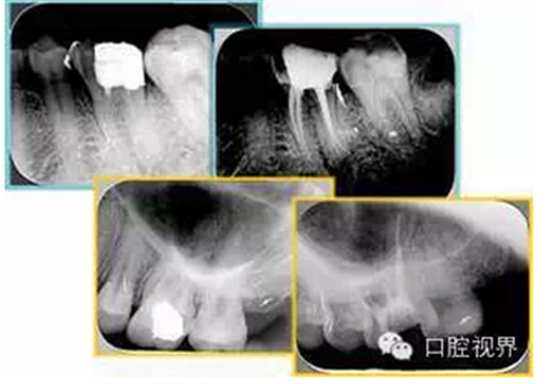

左圖和上圖為干髓治療后牙齒,齲齒疏通后進行根管充填。

( 2 )塑化。

傳統(tǒng)的治療思維:塑化治療后患者需將塑化液清理干凈,達到徹底根管治療目的。

目前的治療思維:以前塑化治療效果好時不必清理干凈塑化液。對于根尖沒有病變的患者,可借助溶解劑建立通路;根尖存在病變的患者往往是塑化治療不理想患者,需要徹底打通通路。

如圖為塑化加根充處理后牙齒 X 線片。